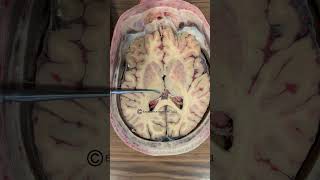

Basal Ganglia video

Basal Ganglia (Basal Nuclei) | Nervous System Neuroanatomy S1 E7: Basal Ganglia #neuroanatomy #ubcmedicine

Neuroanatomy S1 E7: Basal Ganglia #neuroanatomy #ubcmedicine The Basal Ganglia Clinical Anatomy